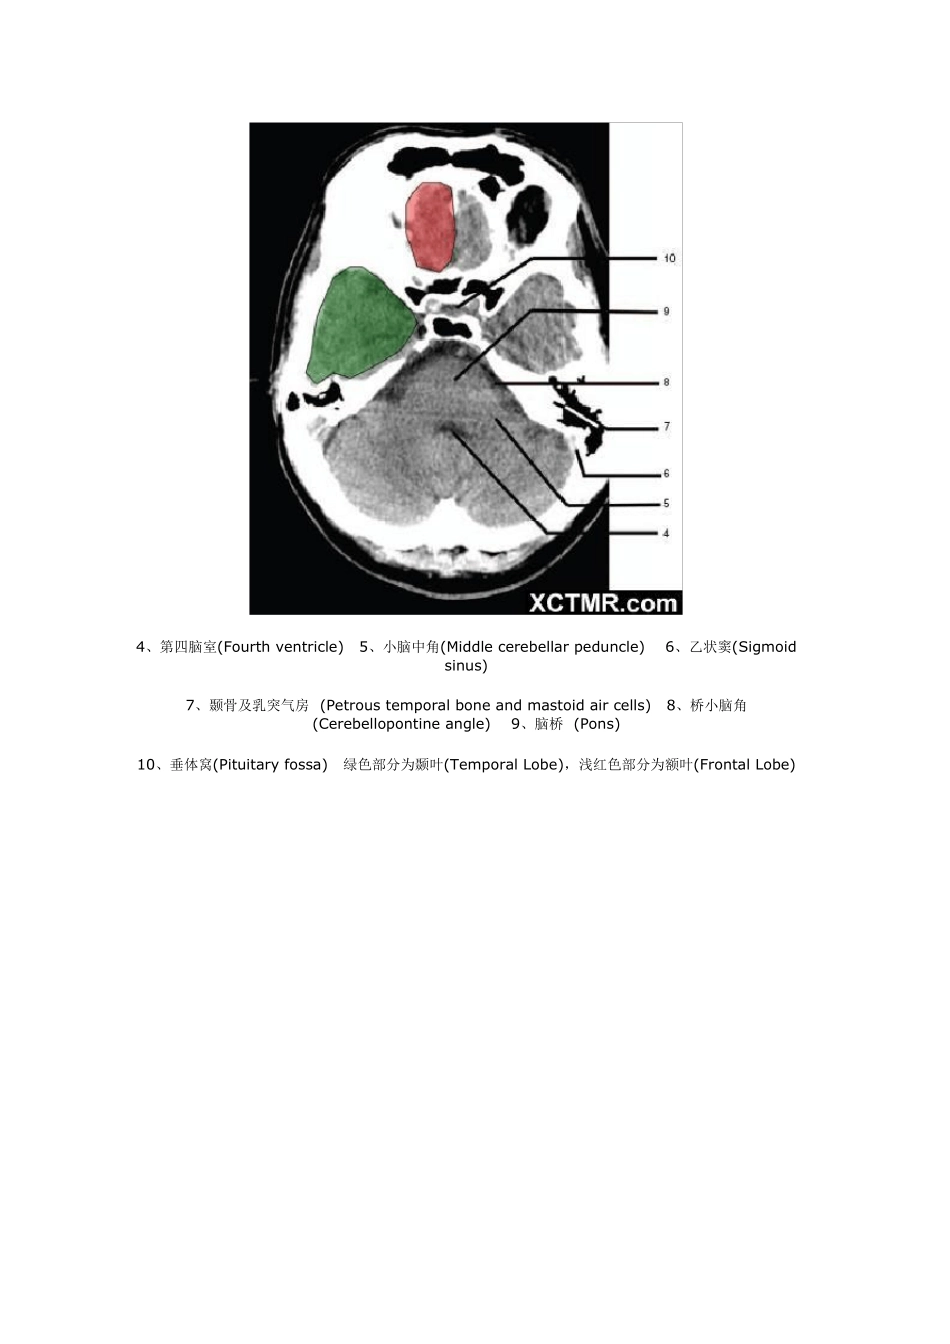

颅脑CT 解剖(图文) 1、蝶窦(Sphenoid sinu s) 2、延髓 (Medu lla oblongata) 3、小脑 (cerebellu m) 绿色部分为颞叶(Temporal Lobe),浅红色部分为额叶(Frontal Lobe) 4、第四脑室(Fourth ventricle) 5、小脑中角(Middle cerebellar peduncle) 6、乙状窦(Sigmoid sinus) 7、颞骨及乳突气房 (Petrous temporal bone and mastoid air cells) 8、桥小脑角(Cerebellopontine angle) 9、脑桥 (Pons) 10、垂体窝(Pituitary fossa) 绿色部分为颞叶(Temporal Lobe),浅红色部分为额叶(Frontal Lobe) 11、小脑蚓部(Cerebellar vermis) 12、基底动脉(Basilar artery) 13、桥前池 (Prepontine cistern) 14、鞍背 (Dorsum sellae) 15、侧脑室颞角(Temporal horn of lateral ventricle) 绿色部分为颞叶(Temporal Lobe) ,浅红色部分为额叶(Frontal Lobe) 16、环池 (Ambient cistern) 17、角间池 (Interpeduncular cistern) 18、大脑角 (Cerebral peduncle) 19、侧裂池 (Sylvian fissure) 绿色部分为颞叶(Temporal Lobe),浅红色部分为额叶(Frontal Lobe) 20、小脑上池 (Third v entricle) 21、侧脑室前角 (Frontal horn of lateral v entricle) 21a、第三脑室 (Third v entricle) 绿色部分为颞叶(Temporal Lobe),浅红色部分为额叶(Frontal Lobe),黄色部分为枕叶(Occipital Lobe) 22、尾状核头部 (Head of caudate nucleus) 23、岛叶 (Insular cortex) 24、外囊 (External capsule) 25、豆状核(Lentiform nucleus) 26、丘脑(Thalamus) 绿色部分为颞叶(Temporal Lobe),浅红色部分为额叶(Frontal Lobe),黄色部分为枕叶(Occipital Lobe) 27、纵裂 (Interhemispheric fissure) 28、内囊前肢 (Anterior limb of internal capsule) 29、内囊膝部 (Genu of internal capsule) 30、内囊后肢(Posterior limb of internal capsule) 31、侧脑室三角区及脉络丛钙化(Trigone of lateral ventricle and calcified choroid plexus) 32、侧脑室枕角(Occipital horn of lateral ventricle) 绿色部分为颞叶(Temporal Lobe),浅红色部分为额叶(Frontal Lobe),黄色部分为枕叶(Occipital Lobe),褐色部分为顶叶(Parietal Lobe) 33、侧脑室体部 (Body of lateral ventricle) 34、放射冠 (Corona radiata) 浅红色部分为额叶(Frontal Lobe),黄色部分为枕叶(Occipital Lobe),褐色部分为顶叶(Parietal Lobe) 35、半卵圆中心 (Centrum semiovale) 浅红色部分为额叶(Frontal Lobe),黄色部分为枕叶(Occipital Lobe), 褐色部分为顶叶(Parietal Lobe) 额骨(FB— Frontal bone) 顶骨(PB — Parietal bone) 枕骨(OB— Occipital bone) 36、中央前回 (Pre-central gyrus) 37、中央沟(Central sulcus ) 38、中央后回 (Post-central gyrus) 浅红色部分为额叶(Frontal Lobe),褐色部分为顶叶(Parietal Lobe) 浅红色部分为额叶(Frontal Lobe),褐色部分为顶叶(Parietal Lobe) 浅红色部分为额叶(Frontal Lobe),褐色部分为顶叶(Parietal Lobe)